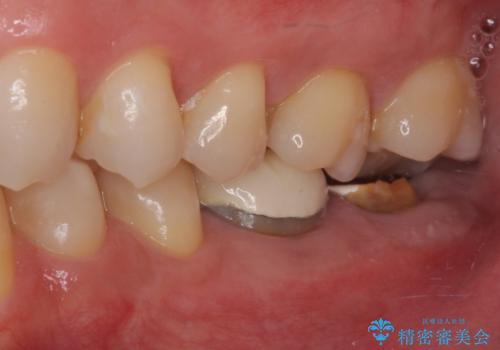

抜歯が必要な奥歯 ストローマン・インプラント補綴治療

- 近医にて奥歯の抜歯が必要と言われたとのことで来院された患者様です。

診査の結果、歯が破折しており、抜歯が必要な状態でした。

最後方歯であるため、入れ歯かインプラントかどちらかの補綴治療を行うこととなりますが、ご希望によりインプラント補綴治療を行うこととしました。

インプラントにはストローマン社のSLActiveを使用し、埋入から補綴までおよそ3か月と、短期間で治療を進めることができました。